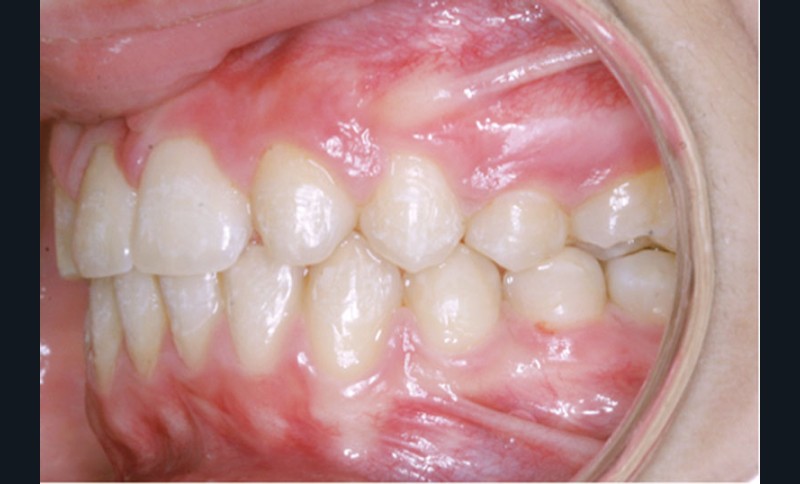

Les photographies de fin de traitement (fig. 4 et 5) montrent la préservation de l’équilibre facial et le respect du profil sous-nasal qui, malgré la croissance, ne s’est pas creusé. Le sourire est très harmonieux et révèle, comme les photographies endo-buccales, la très bonne intégration des canines substituées, après légère coronoplastie de leur pointe.

L’occlusion…